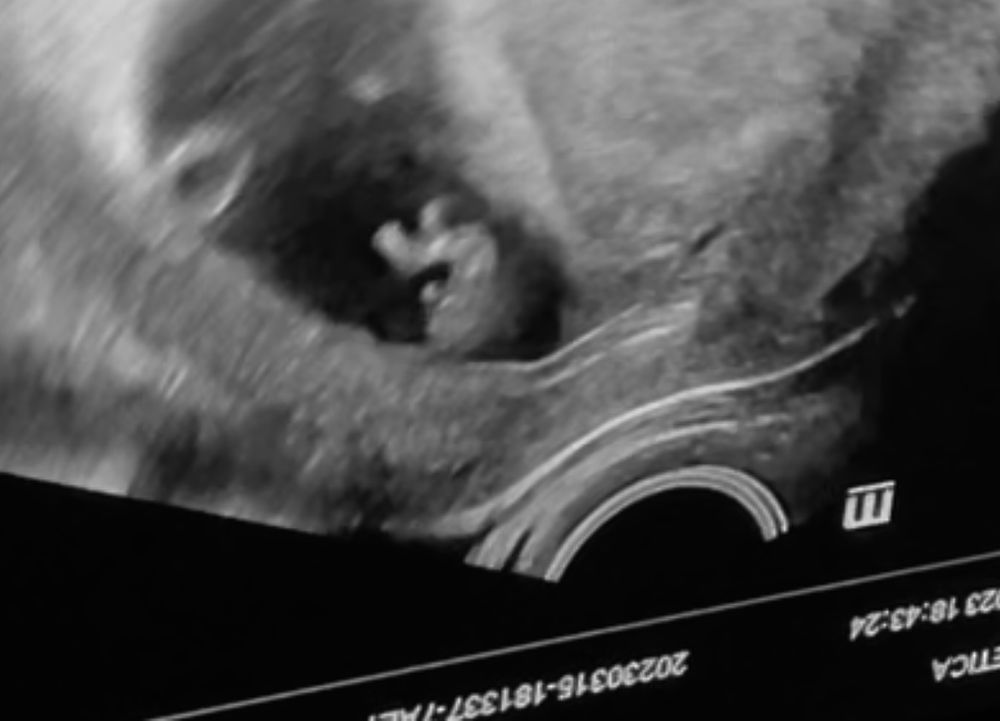

Пупсик такой 🥰